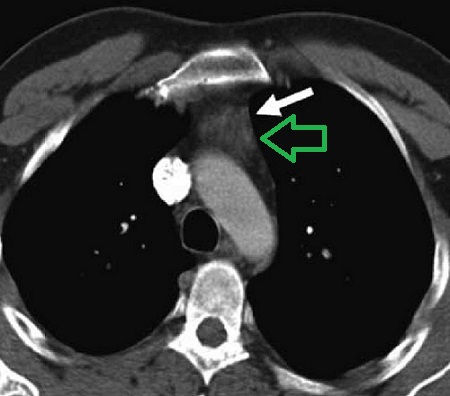

胸腺過形成 CT画像 (JBR–BTR 2012, 95 281-288)

前縦隔に造影効果のある軟部濃度腫瘤を認め、胸腺腫瘍に特徴的な"へ"の字型形態です。

最も鑑別を要する胸腺腫はMRIで内部が不均一に描出される率が高いが、胸腺過形成は内部が均一に描出される(臨床放射線1995;40:825-30)

CTやMRIにおいて、①腫瘤内部に脂肪成分を含むため、まだら状の小結節性低吸収域が見られる、②MR脂肪抑制像(化学シフトMRイメージング)で正常胸腺と同じ生理的な脂肪成分が存在すれば胸腺過形成(Radiology2007;243:869-76)。

脂肪成分を含まない胸腺腫や胸腺癌(悪性胸腺腫、浸潤性胸腺腫)と鑑別されます。